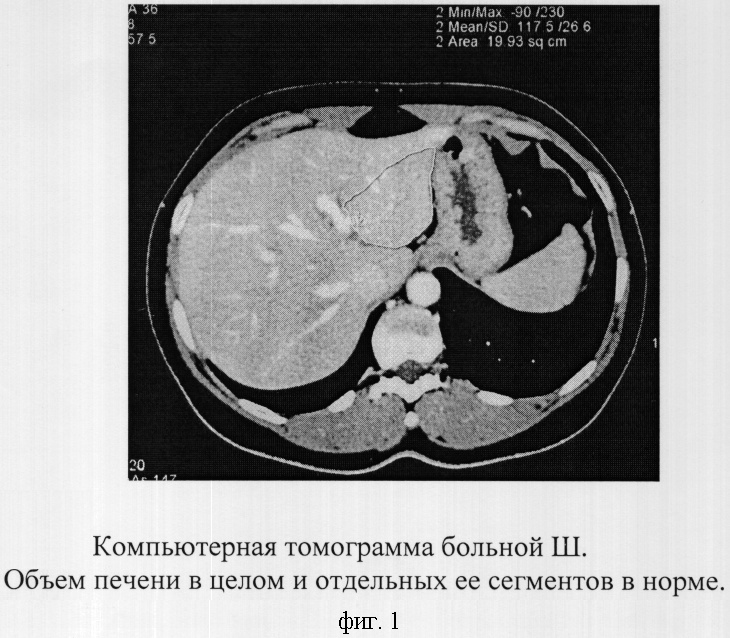

Методы динамического контрастирования печени на МРТ

Раздел: Снимки-подсказки